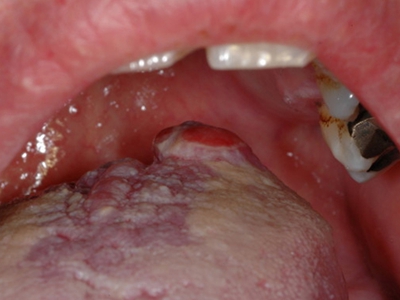

口腔尖锐湿疣是由人乳头瘤病毒感染引起的发生于口腔黏膜的性传播疾病,主要由HPV6、11等型引起。引起尖锐湿疣的某些HPV亚型与癌的发生有关,表现为疣状结节。口腔尖锐湿疣多由口交感染引起,好发生于性活跃的青、中年。

口腔尖锐湿疣好发于舌、牙龈、腭等部位,表现为单个或多个无痛性的疣状结节,有蒂或无蒂,可逐渐增大或融合,形成菜花状、乳头状赘生物,颜色呈肉色或苍白色,患者可有异物感。